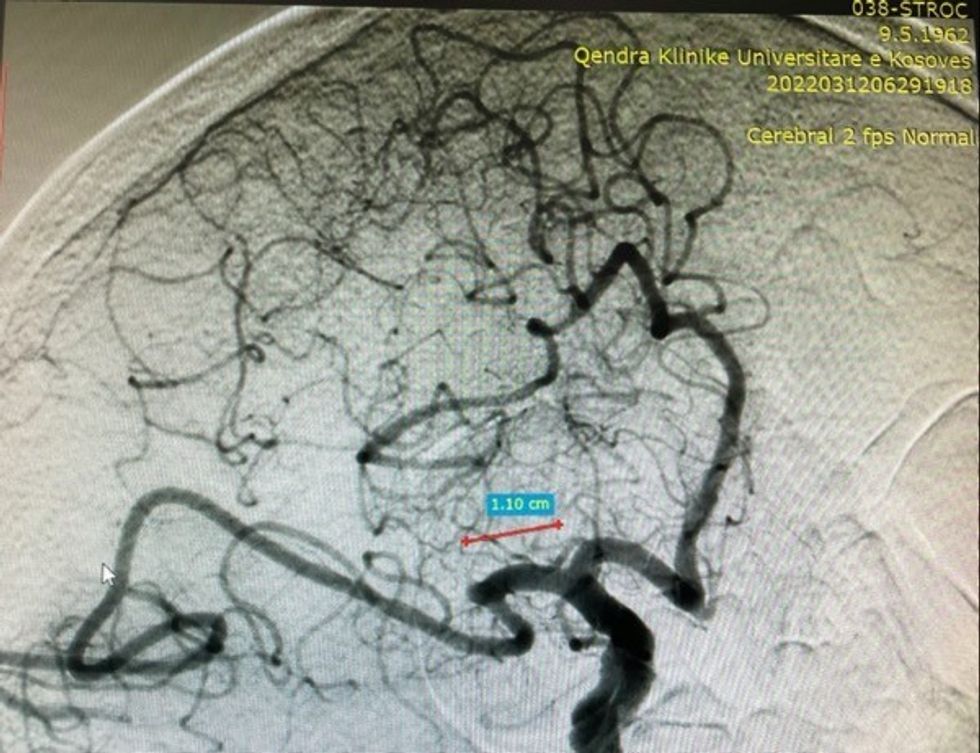

Në ADS imazhe konstatohet mbyllja e arteries trunore të mesme djathtas (ACM).

Okludim – mbyllje e arteries së mesme trunore djathtas (ACM)

Realizohet metoda e kombinuar e trombektomisë mekanike: aspirimi dhe përdorimi i stent retrivier (stentit tërheqës).

Arrihet rihapja – rekanalizimi i arteries së mesme trurore djathtas dhe rivendoshet qarkullimi i plotë i gjakut në tru.

Në imazhet e ADS pas realizimit të trombektomisë, konfirmohet rihapja dhe rivendosja e qarkullimit të gjakut në arterien e mesme trunore djathtas